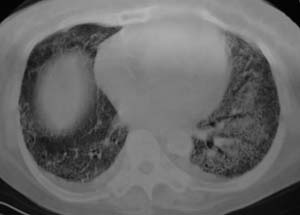

以下是引用liaizhi在2007-7-6 0:05:00的发言:[br]双肺纹理膜糊,沿纹理走行有班点状高密度影。考虑心衰并肺水肿。

以下是引用andymaomao在2007-7-5 22:23:00的发言:[br]双上肺明显,考虑心衰并肺水肿,双侧胸腔少量积液!另不除外肺泡蛋白沉着症及肺泡ca可能。[br]联想机制——心脏病(代偿期)--肺部淤血--后可能并感染致病情加重--抗炎治疗好转,但肺淤血严重,心功能失代偿--心衰而死亡!

以下是引用拾荒者在2007-7-6 13:06:00的发言:[br]支持:心衰,肺水肿及ards